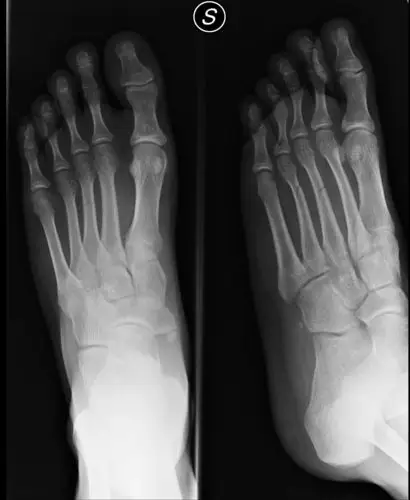

左脚第五跖骨基底部骨折 六月22号骨折.

医学x光片脚掌骨骼